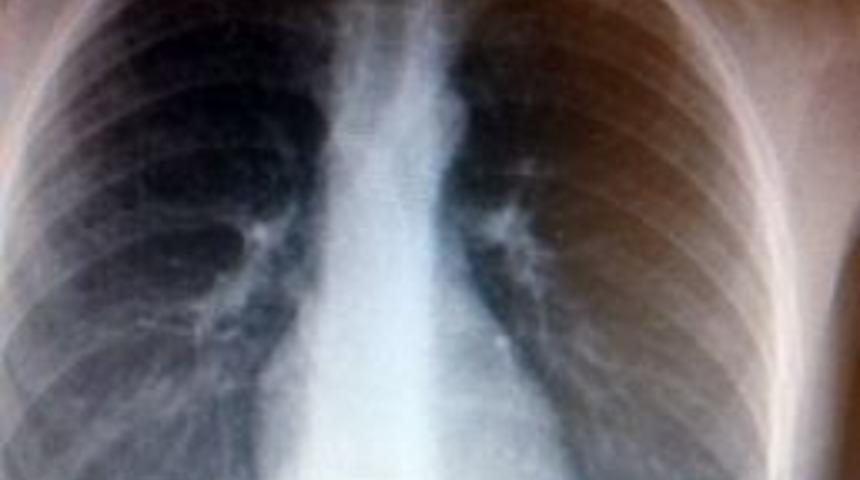

Tekirdağ’ın Çerkezköy ilçesinde 6 yaşındaki E.G., madeni para yuttu. Yemek borusuna takılan para ile ölümden dönen çocuk, “Artık bozuk paralarla oynamayacağım” dedi.Olay, Çerkezköy ilçesinde meydana geldi. Edinilen bilgiye göre, dayısının verdiği harçlıklarla oyun oynadığı sırada halıya düşürdüğü 50 kuruşluk madeni parayı yutan 6 yaşındaki E.G. hastanelik oldu. Durumu fark eden aile önce kendi yöntemleri ile parayı çıkarmaya çalıştı. Tüm müdahalelere rağmen parayı çıkaramayan aile, E.G.'yi Çerkezköy Devlet Hastanesi acil servisine, oradan da 112 sağlık birimlerince Özel Tekirdağ Yaşam Hastanesi'ne götürdü.E.G., Özel Tekirdağ Yaşam Hastanesi Genel Cerrahi Uzmanı Op. Dr. Adem Topaloğlu'nun yaptığı endoskopik girişimle ameliyata gerek kalmadan sağlığına kavuştu.AMELİYATSIZ ÇIKARILDIOp. Dr. Adem Topaloğlu, yapılan tetkikler sonucu paranın yemek borusuna takıldığını saptadıklarını ifade ederek, “Bozuk para yutma şikayeti üzerine ambulans aracılığı ile hastanemize getirilen E.G.’ye yapmış olduğumuz tetkikler neticesinde bozuk paranın yemek borusuna takıldığını saptadık. Endoskopik girişimle Anestezi Uzmanı Dr. Emine Özdemir ile birlikte sedasyon anestezisi sonrası bozuk paranın başarılı bir şekilde çıkarılmasını sağladık” dedi.Başarılı bir endoskopik yöntem sonrasında, yemek borusundan mideye itilen oradan da tıbbi aletler yardımı ile çıkartılan bozuk para, E.G.'nin babasına teslim edildi. E.G., “Beni sağlığıma kavuşturan Yaşam Hastanesi'ne, doktorum Adem Topaloğlu ve ekibine çok teşekkür ediyorum. Bozuk paralarla oynamayacağım” diye konuştu.